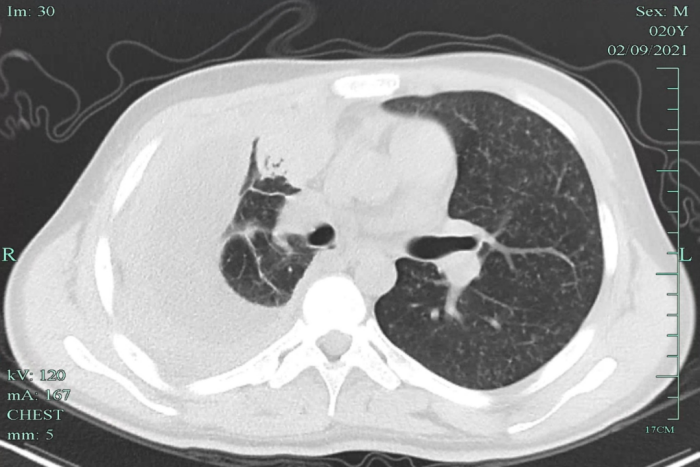

在當(dāng)?shù)蒯t(yī)院檢查,發(fā)現(xiàn)小明兩肺粟粒影,提示可能血行播散性肺結(jié)核,伴有胸腔積液,提示病程比較長了,炎癥反應(yīng)嚴(yán)重。小明立即來到我院感染科就診,隨后住院治療。

經(jīng)全面檢查,小明被診斷為“急性血行播散性肺結(jié)核、結(jié)核性滲出性膿胸”,該類型的肺結(jié)核非常容易引起其他部位的結(jié)核播散,雖然當(dāng)時(shí)小明沒有頭疼頭暈癥狀,但經(jīng)過頭顱磁共振檢查發(fā)現(xiàn),其顱內(nèi)有散發(fā)的結(jié)核病灶。